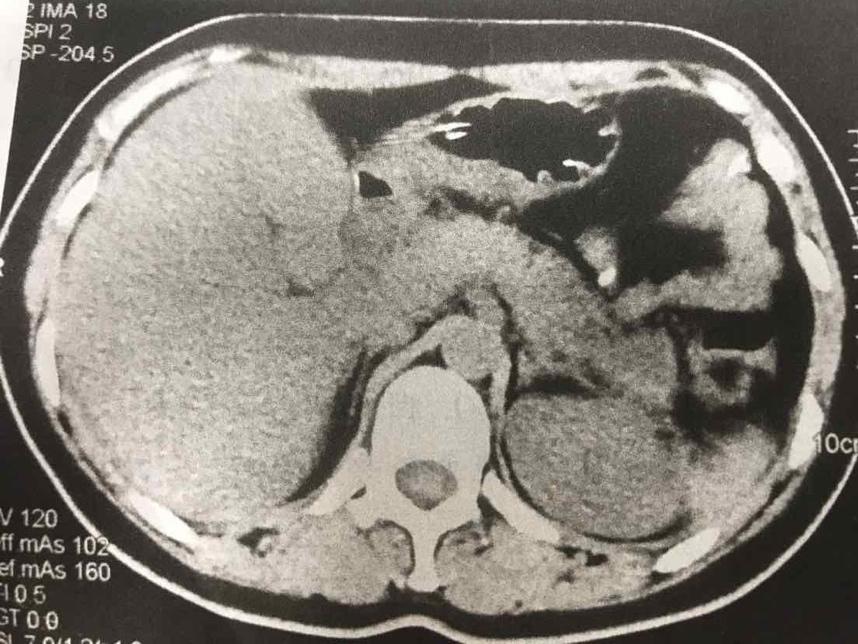

摘要:本文介紹了急性胰腺炎的最新分型,包括其分類標準和特點。文章還提到了一天的奇妙之處與急性胰腺炎分型之間的聯(lián)系,強調(diào)了及時診斷和治療的重要性。全文旨在提高人們對急性胰腺炎的認識,以便更好地預防和治療該疾病。